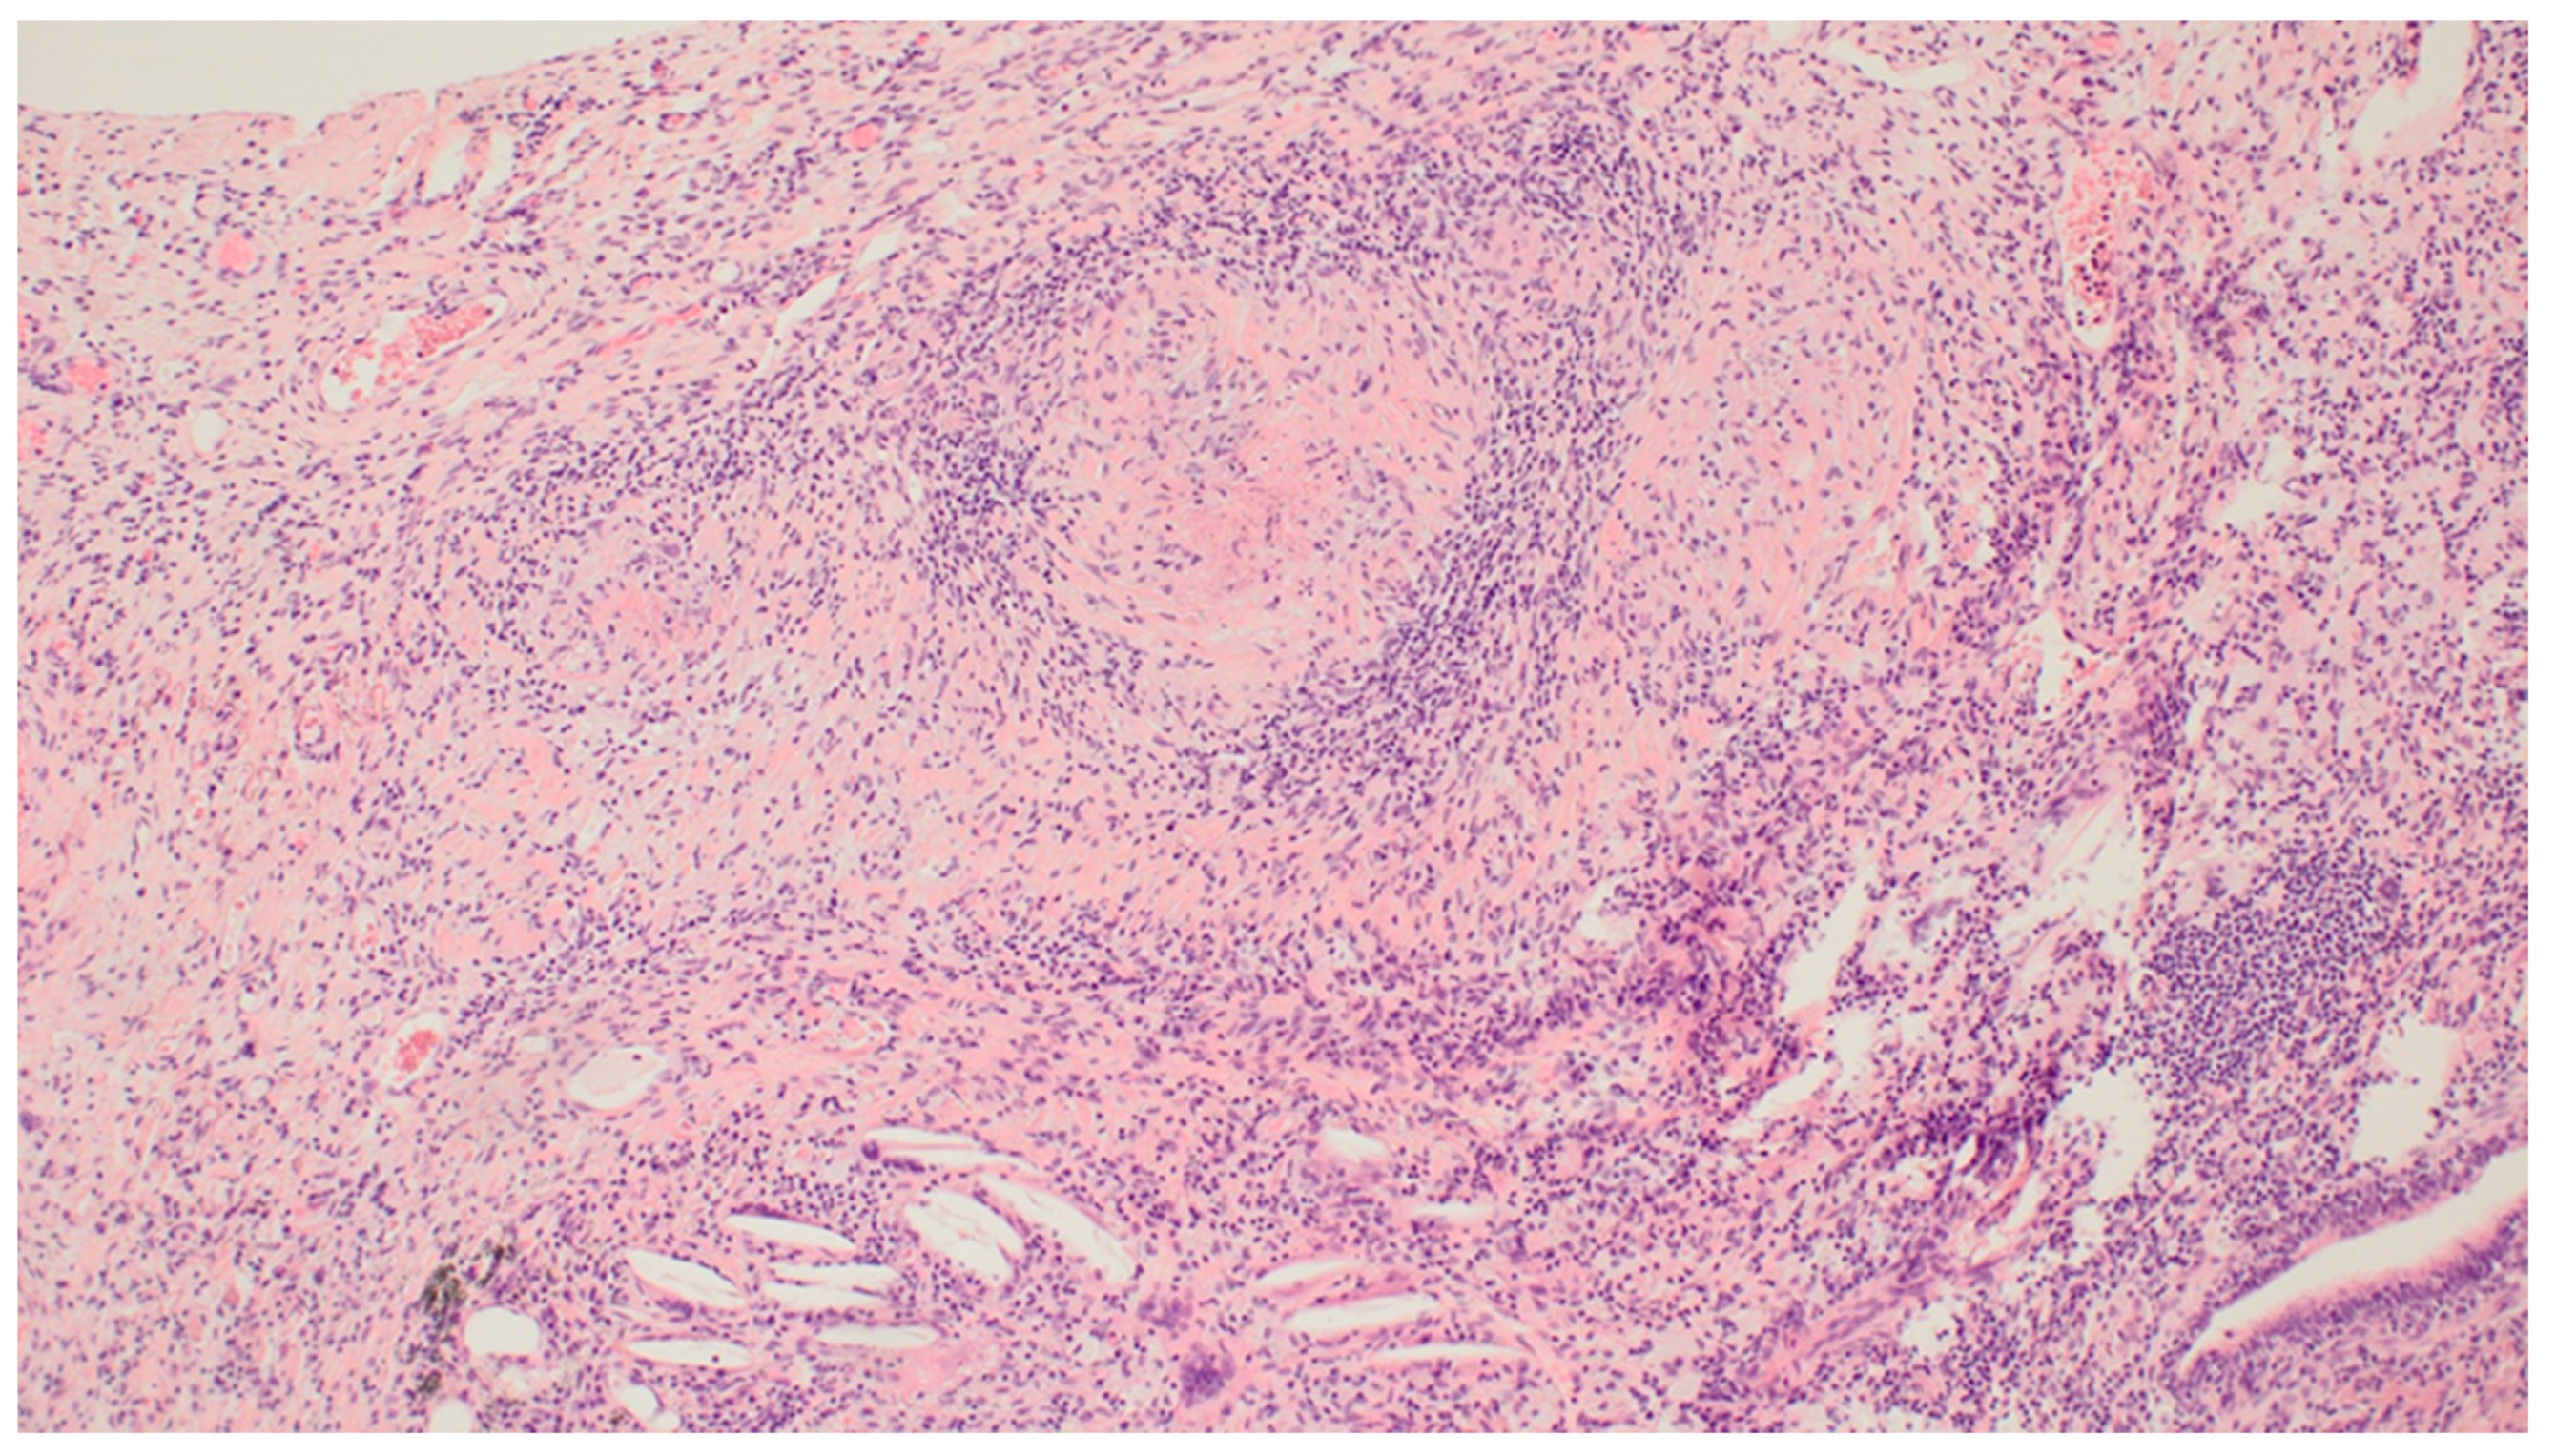

3. Results